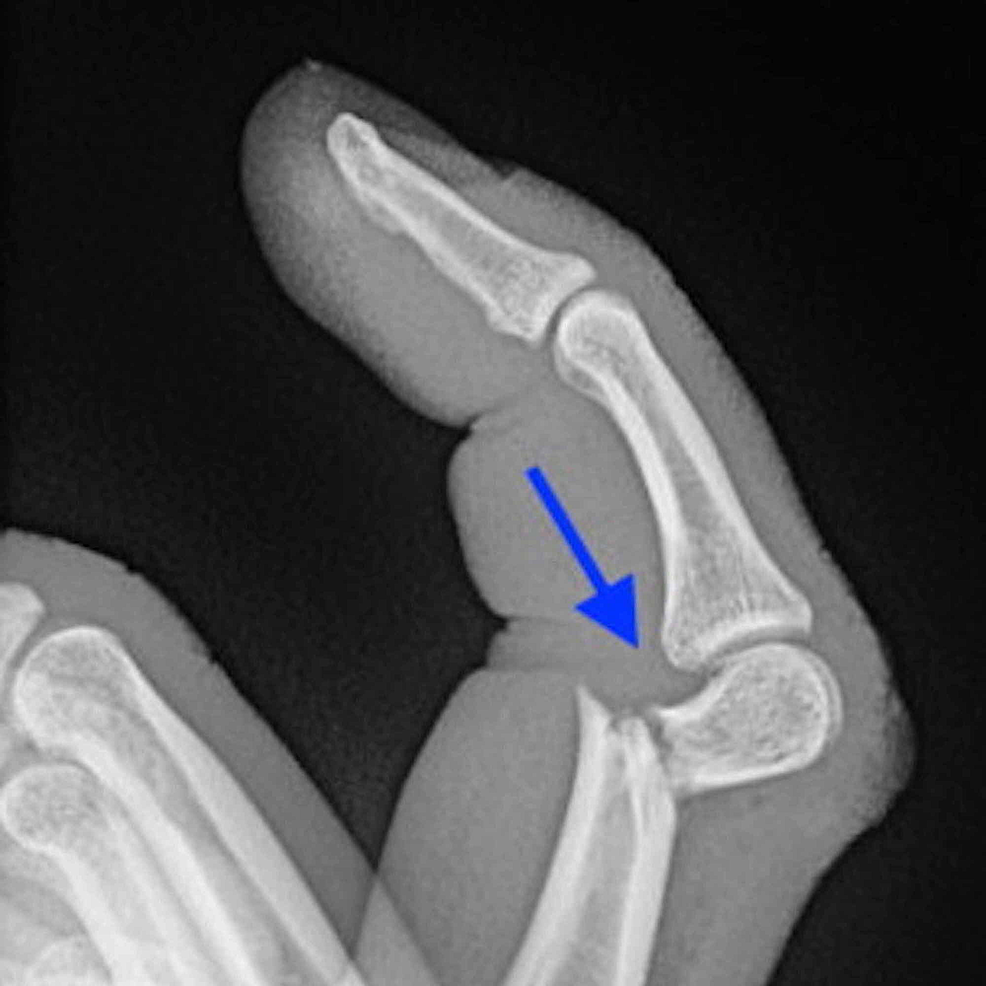

발가락 골절 분류

- 무지(엄지) 골절: 체중 부하가 커서 합병증 위험↑

- 피질부(말단) 파열, 간부(몸통) 골절, 관절 내 골절, 스트레스 프랙처 등으로 세분화합니다.

- X-ray 2 방향 촬영이 1차 진단 표준

- 모호할 경우 CT/MRI 추가

- 수술(핀·스크루 고정)

- 변위 2 mm↑, 관절 선 불일치, 개방 골절일 때 선택